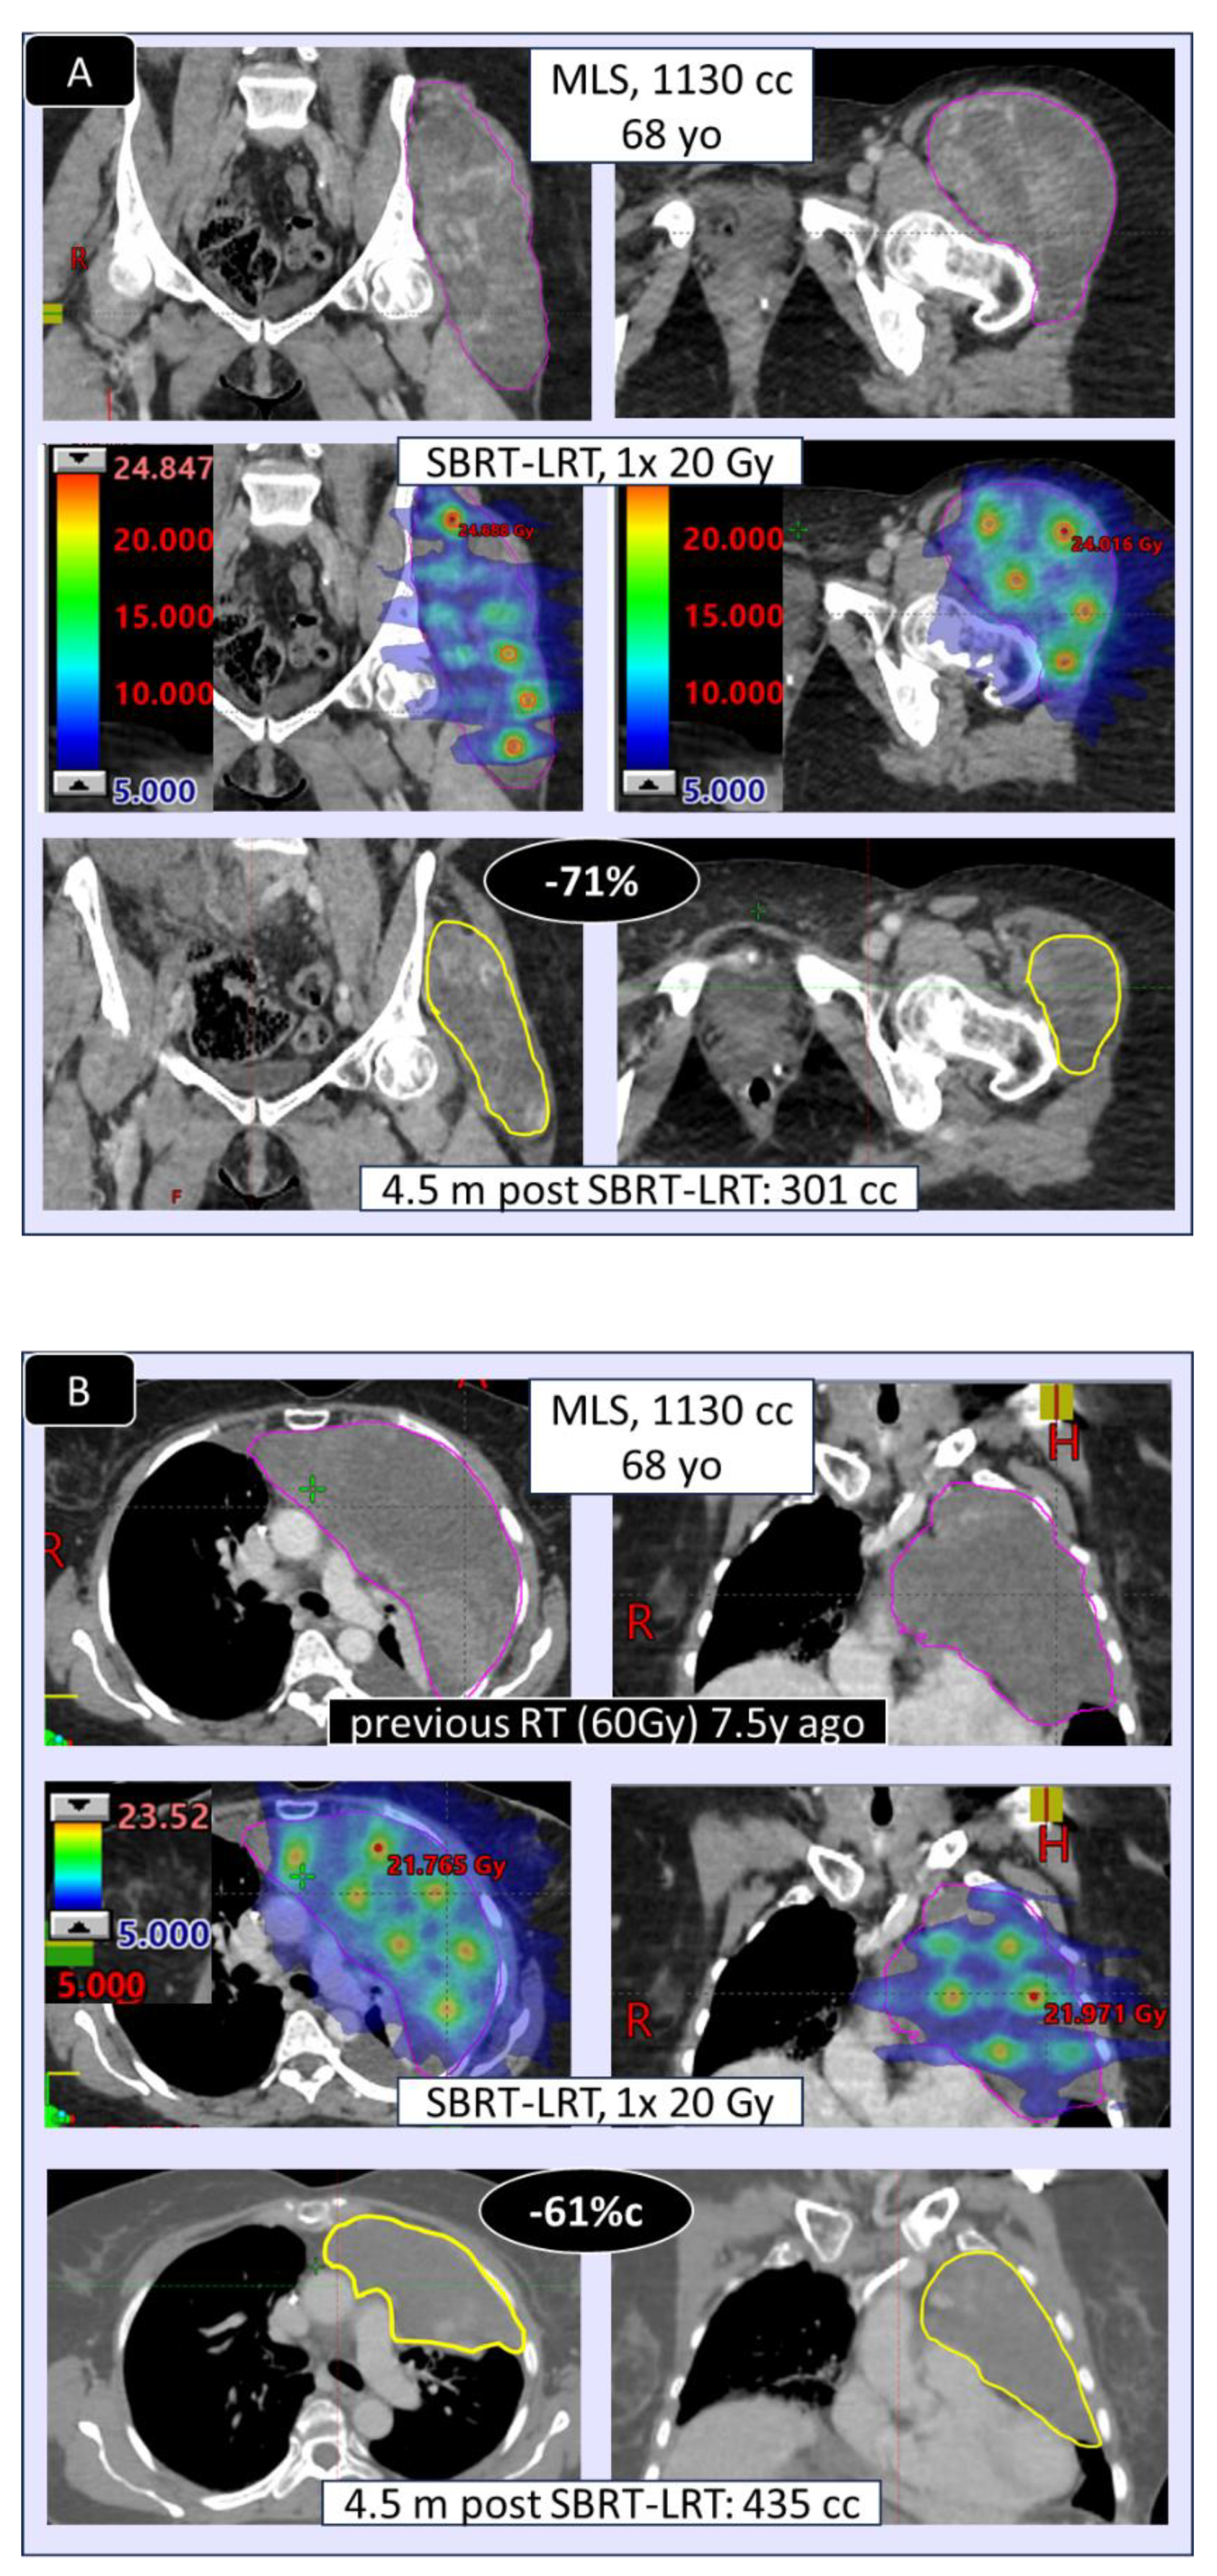

3.2. Radiologic/Volumetric Response, Table 5, Figure 2

| MLS | myxoid liposarcoma |

| UPS | undifferentiated pleomorphic sarcoma |

| •EXTENT of shrinkage, % (mean/median (range) | 53/50 % (15-100) | 55/39 % (14-100) | - |